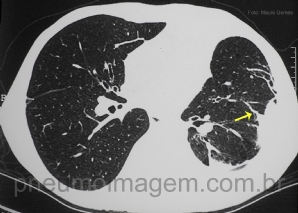

CASO CLÍNICO #24

Essa imagem é característica de uma doença fúngica. Qual o nome desse sinal e a qual doença ele se relaciona? ***** This signal is characteristic of a fungal disease. What is the name of the sign and the disease which it relates?